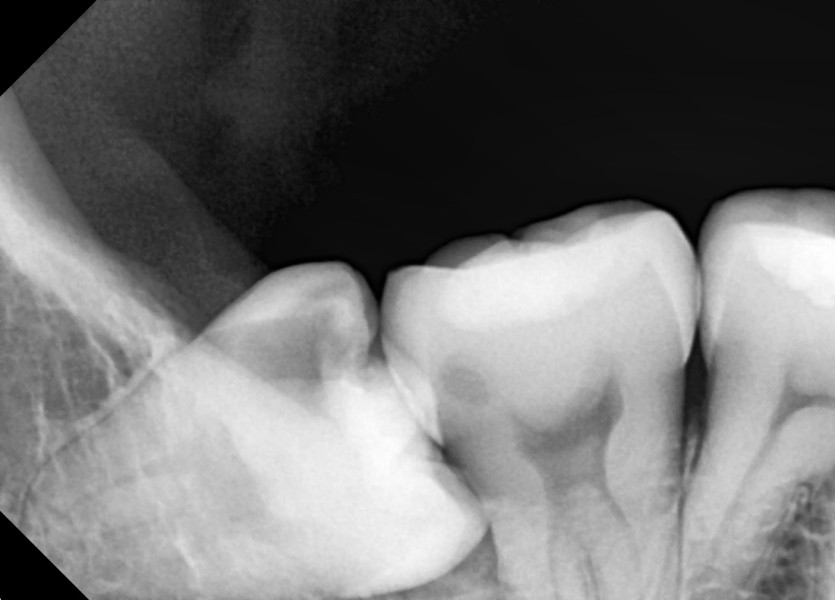

#48 사랑니 발치

구강 외과 전문의가 당일 발치했습니다.